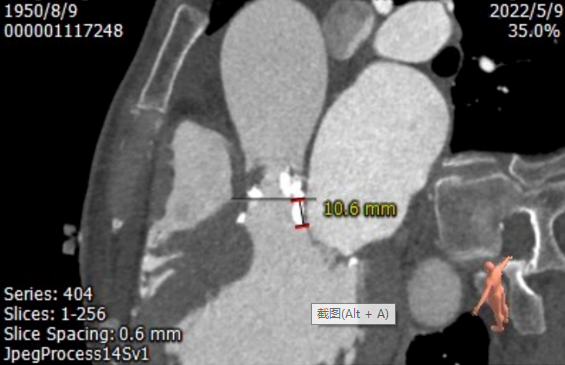

钙化从瓣环延伸至流出道10.8mm

图片

2. 钙化从瓣环延伸至流出道10.6mm,存在瓣周漏风险和瓣环撕裂风险;